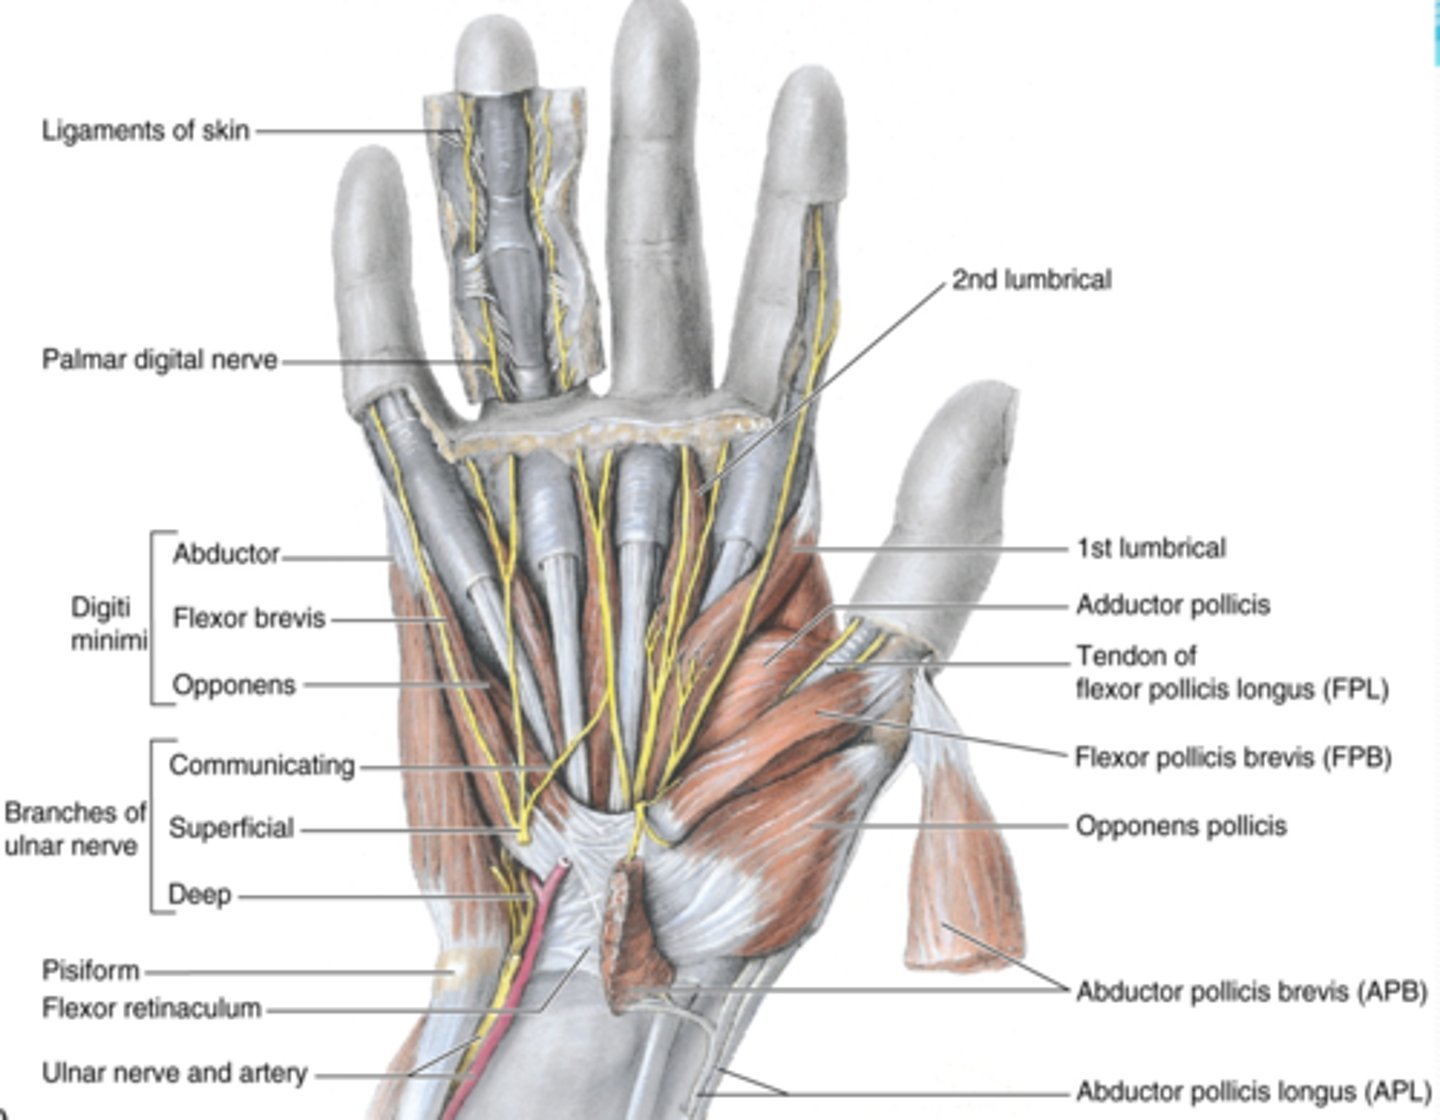

(Muscles of hand:) Muscles of thenar eminence

These muscles are responsible for opposition of thumb

-Abductor pollicis brevis (APB)

-Flexor pollicis brevis (FPB)

-Opponens pollicis

-Abductor digiti minimi

-Flexor digiti minimi

-Opponens digiti minimi

(Muscles of thenar eminence:) Abductor pollicis brevis (APB)

-Abducts 1st digit (thumb), helps opposition

-Median n. (C5 - T1)

-Forms anterolateral part of thenar eminence

(Muscles of thenar eminence:) Flexor pollicis brevis (FPB)

-Flexes 1st digit (thumb)

-Median n. (C5 - T1)

-Medial to APB

(Muscles of thenar eminence:) Opponens pollicis

-Opposes 1st digit (thumb)

-Median n. (C5 - T1)

-Deep to APB

(Muscles of thenar eminence:) Abductor digiti minimi

-Abducts 5th digit

-Ulnar n. (C7 - T1)

-Most superficial of the hypothenar muscles

(Muscles of thenar eminence:) Flexor digiti minimi

-Flexes 5th digit

-Ulnar n. (C7 - T1)

-Lateral to abductor digiti minimi

(Muscles of thenar eminence:) Opponens digiti minimi

-Rotates 5th digit bringing it into opposition with the thumb

-Ulnar n. (C7 - T1)

-Deep to abductor and flexor digiti minimi muscles

Short muscles of hand

lumbricals, dorsal interossei (4) , palmar interossei (3)

(Short muscles of hand:) Lumbricals

-Flex fingers at metacarpophalangeal joints and extend interphalangeal joints of 2nd - 5th digits

-Median n. (C5 - T1)

(Short muscles of hand:) Dorsal interossei (4)

-Abduct fingers

-Ulnar n. (C7 - T1)

-Between the metacarpal bones

(Short muscles of hand:) Palmar interossei (3)

-Adduct fingers

-Ulnar n. (C7 - T1)

-On the palmar surface of metacarpal